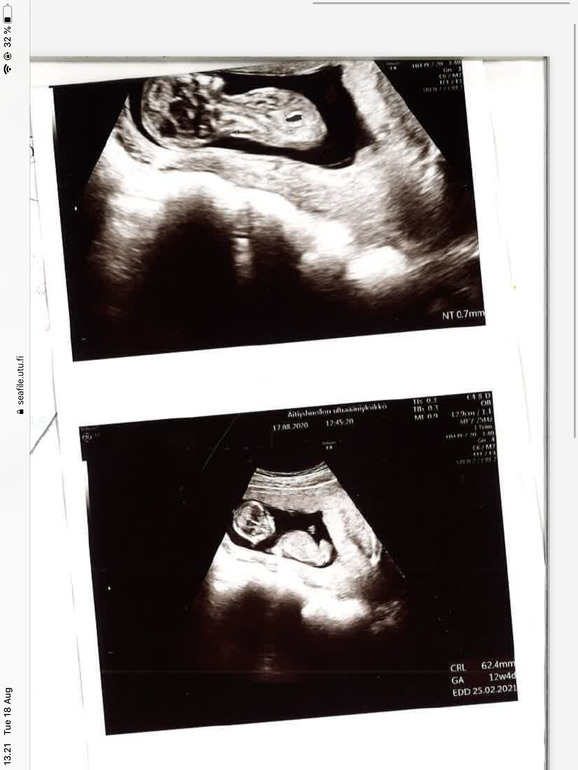

Первый скрининг 12+1

Прошла узи скрининг, все весьма неплохо и кроха на 12+4, муж почти рыдал от счастья, я спокойней тк уже была на 9 неделе и познакомилась с малышком. Посмотрите пожалуйста девочка или мальчик ? Ребёнок первый и скорее всего единственный, так что предпочтений нет, просто интересно. Спасибо!

Врач работал очень быстро, бесплатный скрининг оч отличается от платного узи, удивительно что картинки распечатали, схожу недель в 15 посмотреть ребетенка а то после зб оч некомфортно